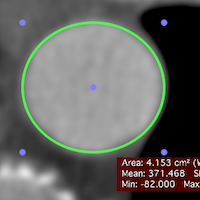

OsiriX 7.5 New features

Click on the thumbnails to have a closer look at each new feature.

Faster GUI

Faster GUI